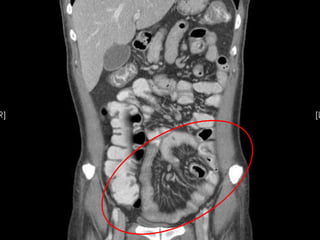

Pt underwent CT scan of the abdomen

• Work up :

 CT abdomen and pelvis with IV contrast

FINDINGS :

Multiple mesenteric lymphadenopathies

, largest one measuring 1.7cm.

Mild hepatomegaly.

Jejunization of the ileum